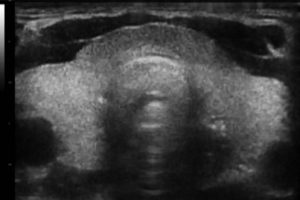

Diplomados en Ultrasonografía